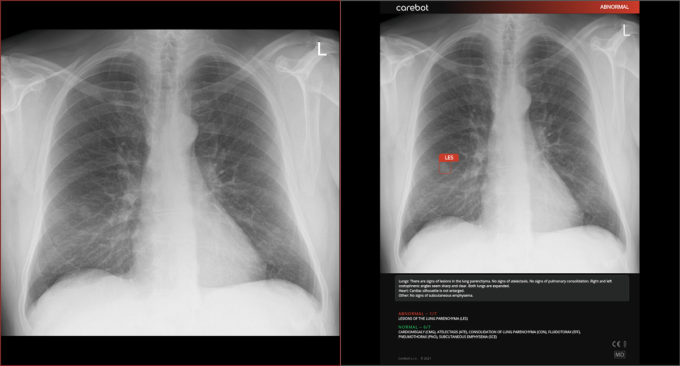

Czech AI company and Bristol Myers Squibb announced a collaboration to improve early detection of lung cancer. This innovative partnership will enable the integration of Carebot, a solution that assists physicians in evaluating X-ray images to increase diagnostic accuracy and accelerate the identification of early-stage lung cancer.

Lung cancer is among the most challenging cancers to detect, with delayed diagnosis often reducing the chances of effective treatment. With Carebot’s artificial intelligence, healthcare professionals can analyze chest X-rays with high accuracy and rapidly identify abnormalities that may indicate early-stage lung cancer. The company’s artificial intelligence, Carebot, holds the potential to analyze thousands of chest X-rays in a fraction of the time required for manual evaluation, which can increase diagnostic accuracy by up to 20% and reduce diagnosis time by up to 30%.

As part of the pilot project, the technology will be rolled out in five selected hospitals in the Czech Republic. Healthcare professionals, accompanied by AI, will evaluate all chest X-rays. “Carebot’s artificial intelligence is implemented directly into the system we commonly use for diagnosis. Less experienced doctors often assess chest X-rays. The AI notifies them of even small lesions that might otherwise be missed,” said Pavel Struna, Head of the Radiology Department at the Slaný Hospital.